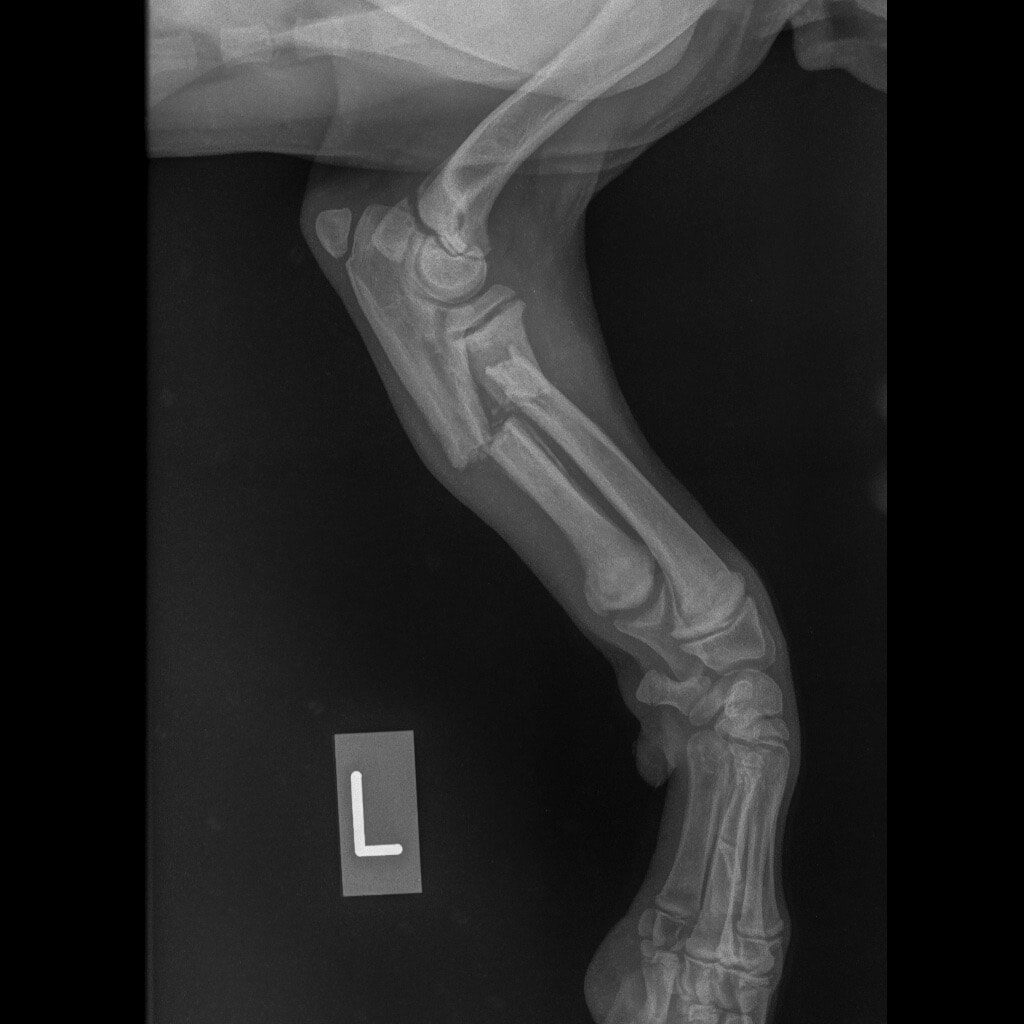

Ο Νικόλας βρέθηκε από εθελοντές και μεταφέρθηκε σε κτηνιατρείο. Δύο μπροστινά σπασμένα πόδια, πληγές, τσιμπούρια, ψύλλοι. Αυτή ήταν η κατάστασή του.

Η Maria Arkomani αναφέρει χαρακτηριστικά: «Δυστυχώς πολλοί ορθοπεδικοί έλειπαν και κάποιοι άλλοι δεν αναλάμβαναν το χειρουργείο του λόγω δυσκολίας και συγχρόνως επειδή είχαν περάσει μέρες από το σπάσιμο. Αμέσως πήγαμε στο κτηνιατρείο της Lena Kon για να δοθούν οι πρώτες βοήθειες από τον Νίκο Μαργαρίτη όπου τον ευχαριστούμε από καρδιάς. Βγήκαν ακτινογραφίες και έδειξαν τη ζημιά που είχε υποστεί αυτό το πλάσμα. Στο ένα πόδι μπήκε γύψος αλλά το άλλο ήθελε χειρουργείο. Στείλαμε σε πολλούς γιατρούς τις ακτινογραφίες αλλά οι απαντήσεις ήταν αρνητικές καθώς ήταν δύσκολο το χειρουργείο σε να κουτάβι με τέτοιο πρόβλημα. Ο μοναδικός γιατρός που μας απάντησε άμεσα και μπόρεσε να αναλάβει τον Νικόλα μας και να πάρει το ρίσκο του χειρουργείου είναι ο ορθοπεδικός Antonios Lionakis. Ένα χειρουργείο πάρα πολύ δύσκολο, με ρίσκο αλλά πρέπει να γίνει..»